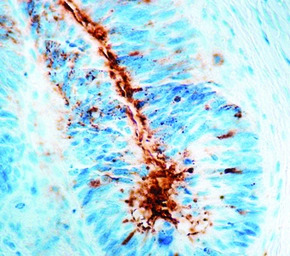

IHC-P analysis of human breast carcinoma tissue using GTX21320 TAG72 antibody [B72.3] (ready-to-use).